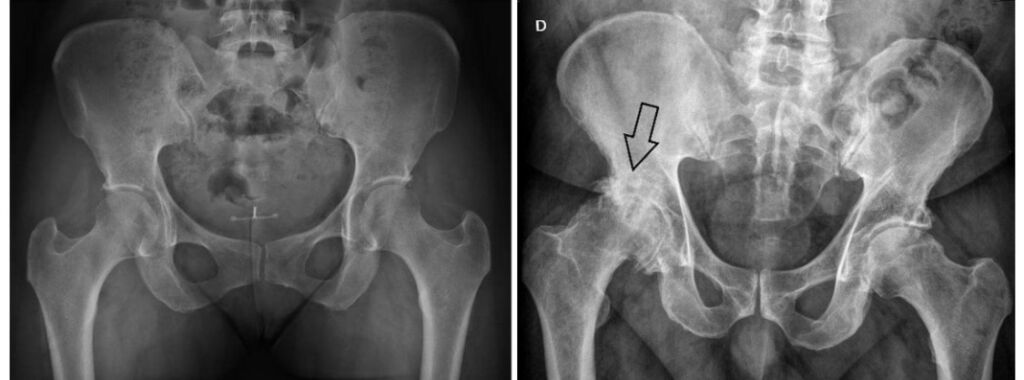

A decisão pela cirurgia deve ser individualizada e baseada em três pilares principais: intensidade da dor, limitação funcional e impacto na qualidade de vida. Não se trata apenas de uma imagem de raio-X, mas de como o paciente vive no dia a dia.